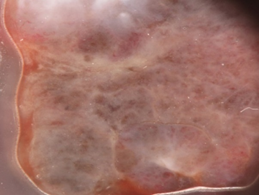

Figure 1. Clinical (a), dermoscopic (b) and RCM (c,d) aspect of a hypomelanotic mucosal melanoma. (b) Dermoscopy shows structureless grey and white color and remnants of pigmentation. (c,d) Reflectance confocal microscopy features at the epidermal level (images acquired with VivaScope 3000, Caliber, New York, USA): atypical cells are indicated by red arrows.

From these studies, mucosal melanoma seems to be characterized by these major features: presence of pagetoid hyper-reflective large cells in the epithelium (mainly roundish or dendritic), high density of basal hyper-reflective large dendritic and round cells and loss of normal architecture of chorion papillae. Data on amelanotic and hypomelanotic mucosal melanoma are lacking; in our experience, atypical cells are still well visible although they are less hyper-reflective and lose reflectance moving from the surface to the inner part of the tumor (Figure 1).